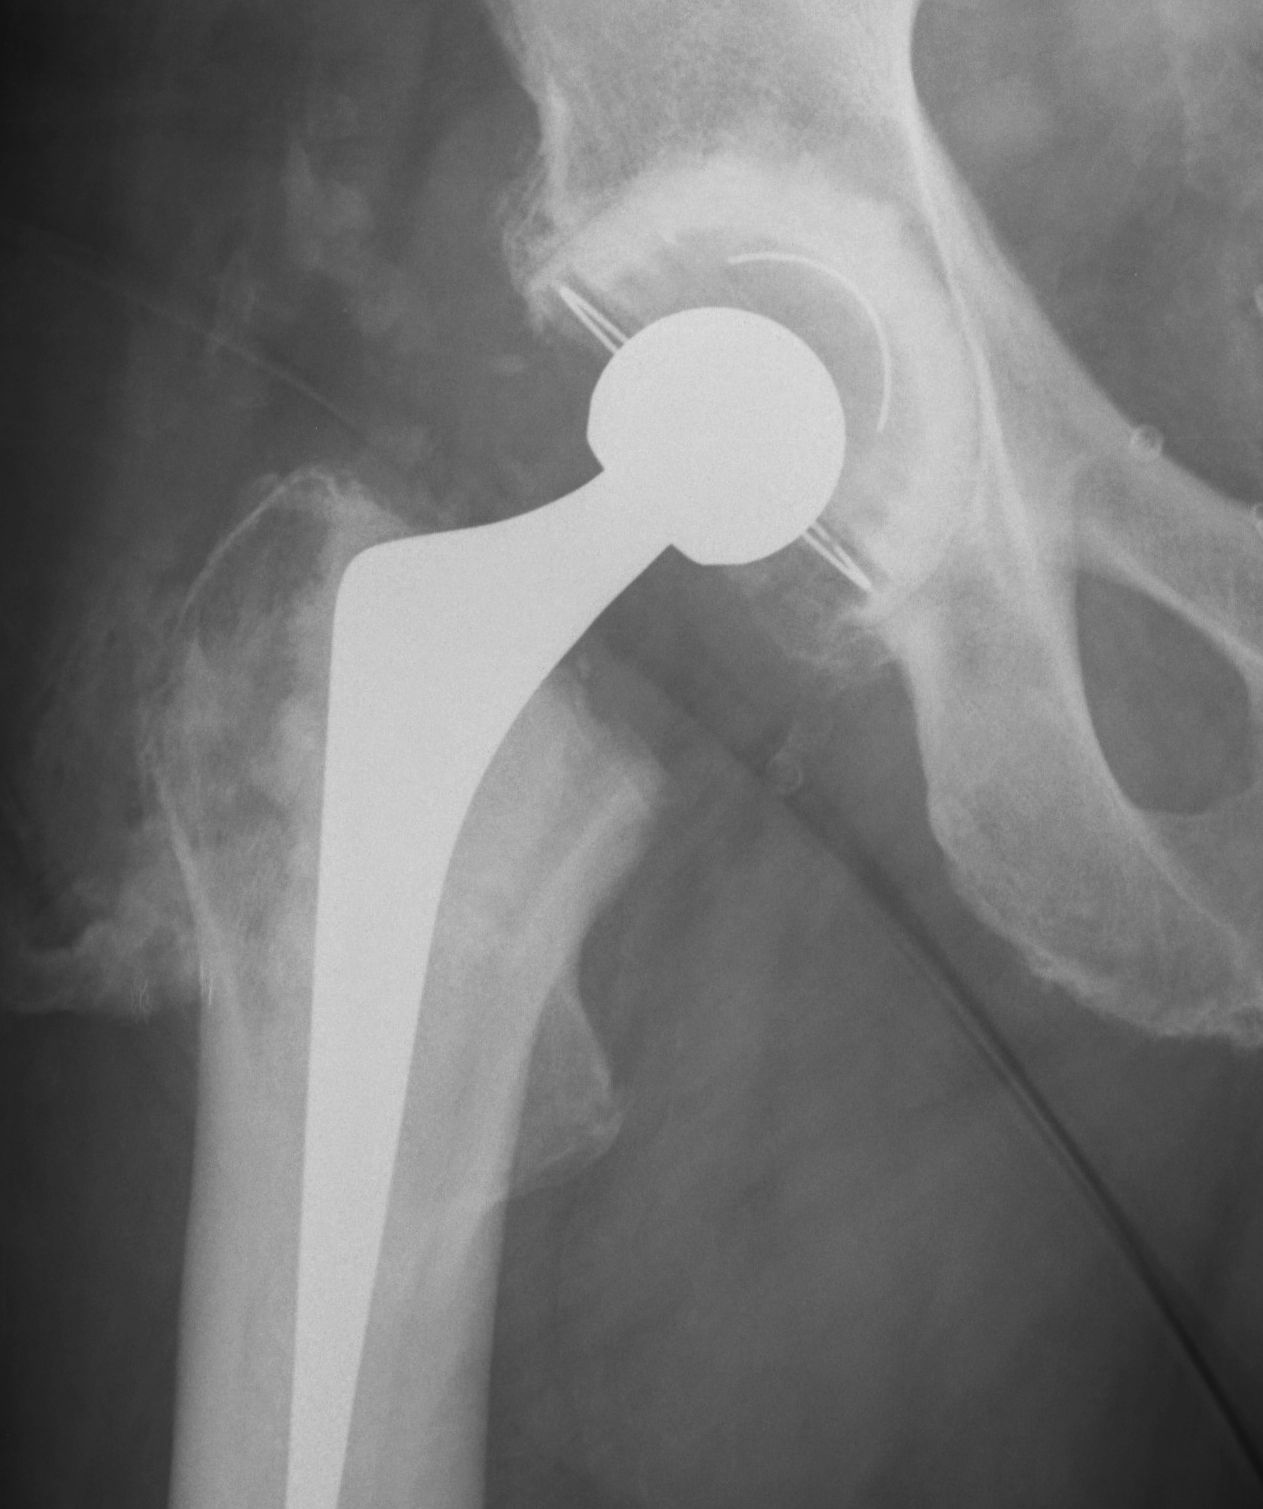

Brooker Classification: Type III and Type IV clinically relevant

Type I: Isolated islands of bone

Type II: Bony spurs from pelvis and proximal femur, gap > 1 cm

Type III: Gap < 1 cm

Type IV: Apparent ankylosis